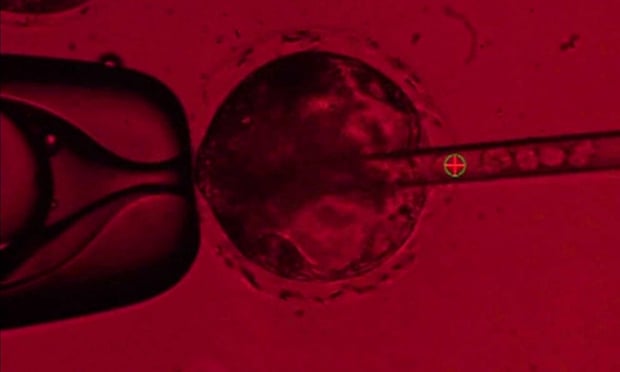

Researchers at the University of California, Davis

combined human stem cells and pig DNA and allowed the embryos to mature for 28

days, before terminating the experiment and analysing the tissue.